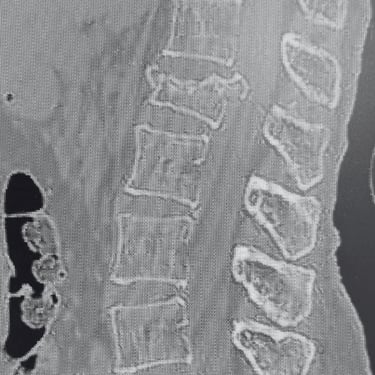

🧠 Estenosis Lumbar | Laminectomía Descompresiva Lumbar.

La laminectomía descompresiva lumbar trata la estenosis severa mediante retiro de láminas y ligamentos comprimidos, liberando las raíces nerviosas. La cirugía microquirúrgica preserva la estabilidad de la columna, reduce daño muscular y permite recuperación funcional rápida, aliviando dolor y mejorando movilidad, facilitando el retorno seguro a las actividades cotidianas.